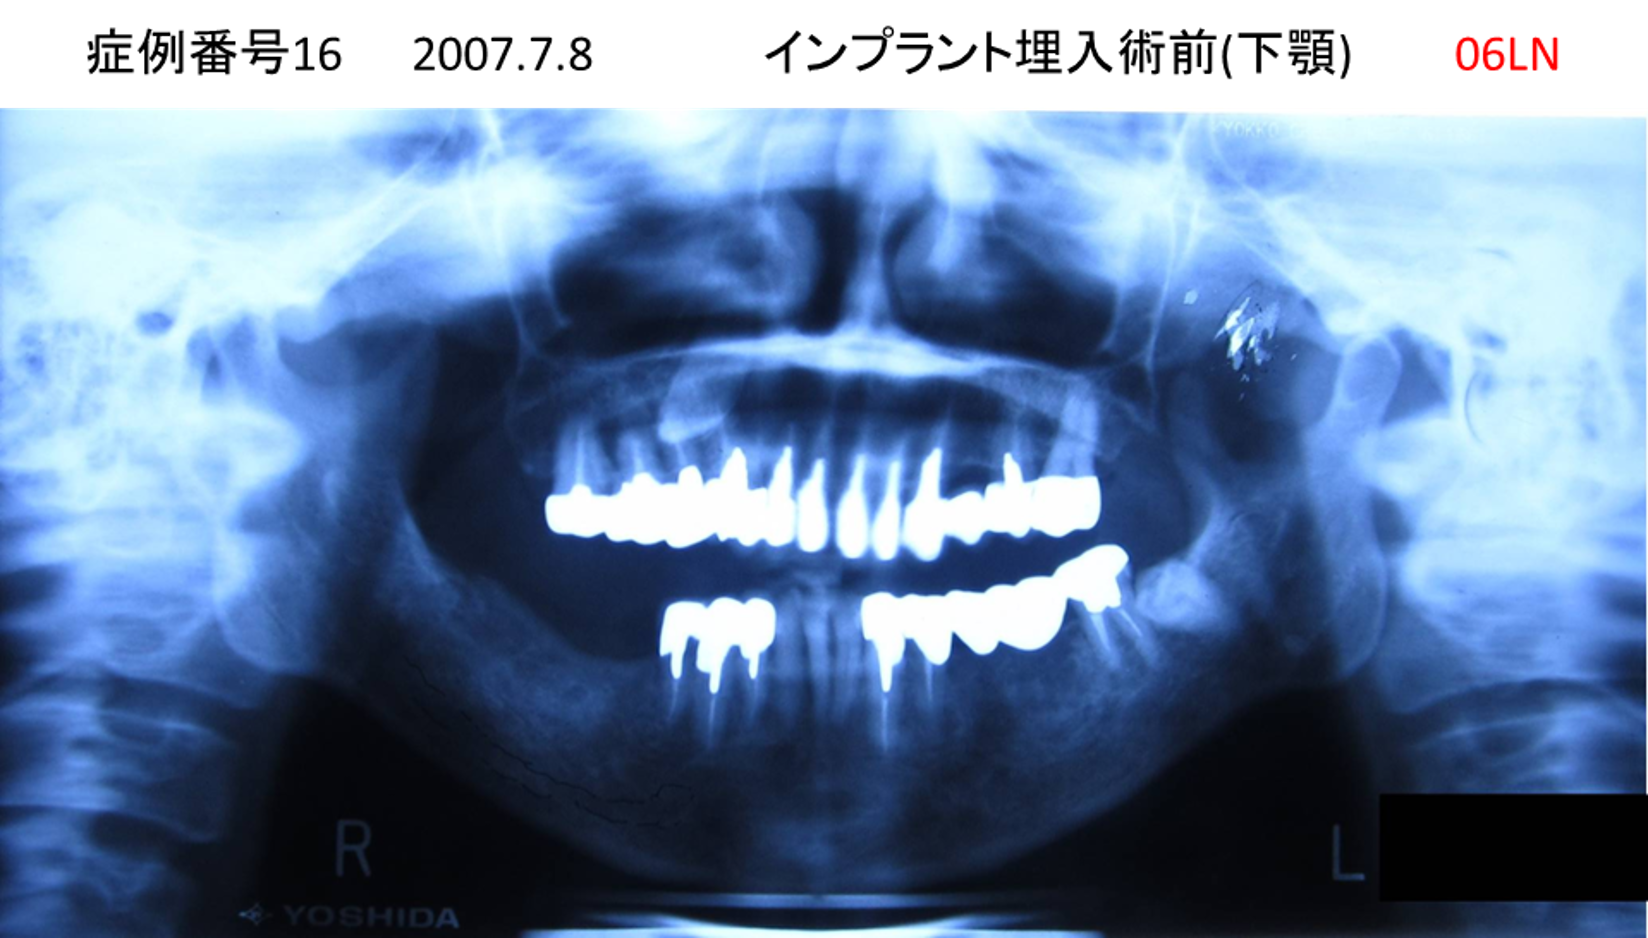

義歯が合わない、噛めない患者様のインプラント症例

| 治療名称 |

インプラントコーヌステレスコープ |

| 治療費用 |

270万円+税 |

| 治療期間 |

4か月 |

| 患者さんの症状(主訴) |

義歯が合わない、噛めない |

| 治療内容 |

インプラント、義歯作製(コーヌステレスコープ) |

| 治療結果 |

しっかり噛めるようになった。見栄えが良くなった。 |

| 治療の注意点(リスク/副作用) |

義歯が壊れた場合、インプラントが壊れた場合は再治療が必要 |